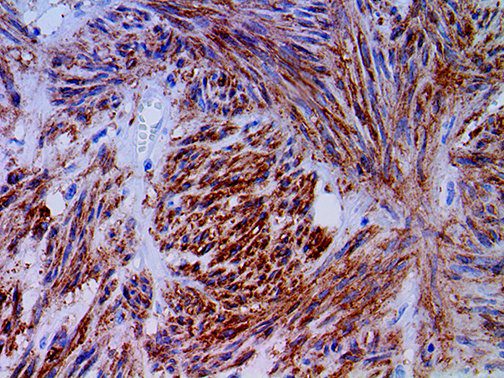

It is the ICU physician who is most likely to witness one of the deadliest manifestations of the abnormal immunological response, the cytokine storm syndrome (CSS). This response is also referred to by some as the cytokine release syndrome (CRS). CSS is characterized by continuous activation and expansion of macrophage and lymphocyte populations, which secrete large amounts of cytokines, causing the cytokine storm. This massive cytokine release is akin to hemophagocytic lymphohistiocytosis (HLH) disease, a syndrome characterized by initial unchecked and persistent activation of cytotoxic T lymphocytes and NK cells.

Clinical and laboratory manifestations of HLH include fever, enlarged liver and/or spleen, neurologic dysfunction, coagulopathy, liver dysfunction, cytopenias (i.e., low levels of erythrocytes, leukocytes, and/or platelets), hypertriglyceridemia, hyperferritinemia, hemophagocytosis, and eventually diminished NK cell activity as the immune system becomes progressively paralyzed. HLH can be familial (primary HLH) or secondary to another disease process (sHLH), such as rheumatic disease, in which it is referred to as macrophage activation syndrome (MAS, characterized by elevated ferritin).